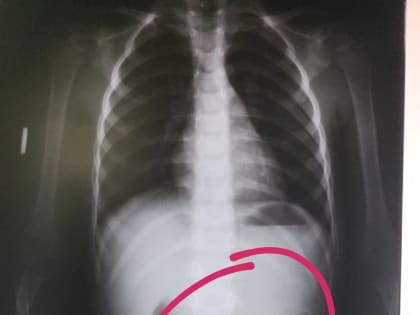

Фото:Раевская ЦРБ В Башкирии медики обнаружили в животе трехлетнего ребенка цепочку.